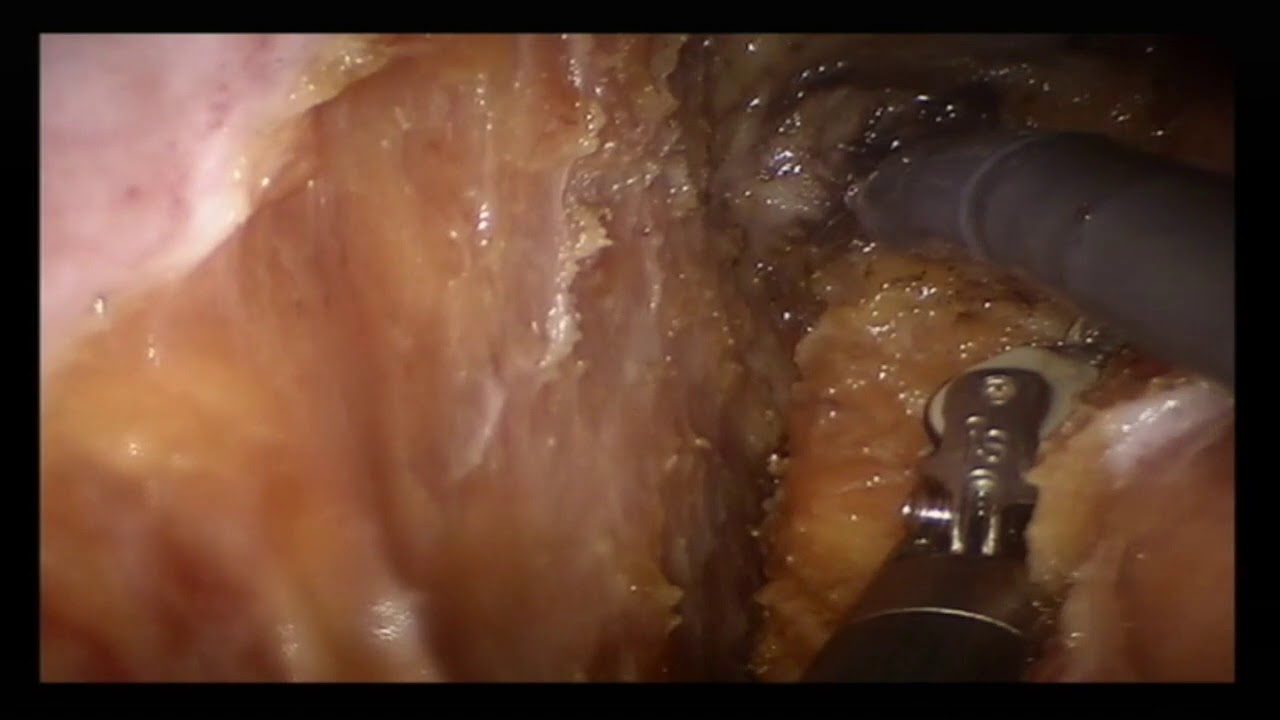

This video edit shows the performance of a low anterior resection with total mesorectal excision for a rectal cancer AND a radical prostatectomy for a synchronous adenocarcinoma of the prostate gland in the same operation in the one patient. Two surgical teams are involved both using the same Da Vinci robotic system. This video is associated with a text under submission for publication in the journal Colorectal Disease.

Authors: Nicola de’Angelis MD, PhD (1), Alexandre Ingels MD, PhD (2), Alexandre de La Taille MD, PhD (2) and Francesco Brunetti, MD(1).

(1) Unit of Digestive of Digestive Surgery, Henri Mondor Hospital, AP-HP, University of Paris Est, UPEC, Créteil, France.

(2) Unit of Urology, Henri Mondor Hospital, AP-HP, University of Paris Est, UPEC, Créteil, France.